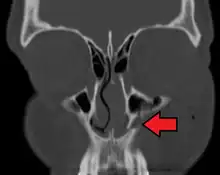

Fracture of the left lacrimal / maxillary bone

A maxilla fracture is a form of facial fracture. A maxilla fracture is often the result of facial trauma such as violence, falls or automobile accidents. Maxilla fractures are classified according to the Le Fort classification.